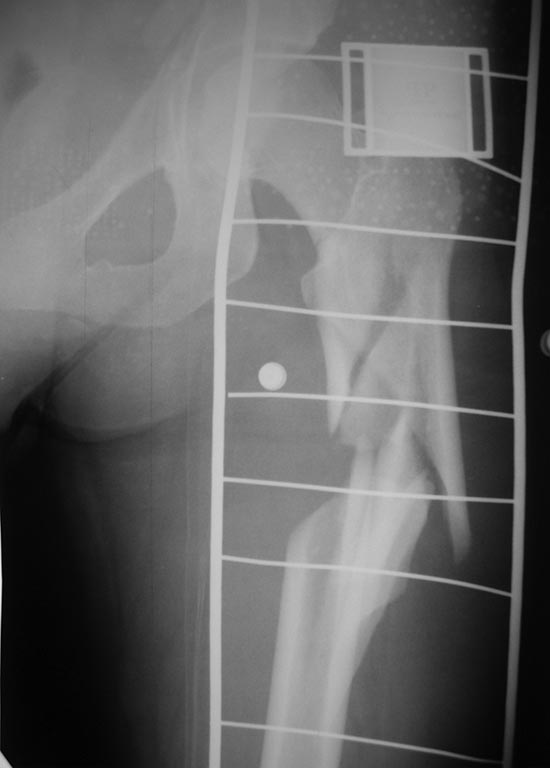

Травма 31.12.13 в результате ДТП (столкновение а/машин). Находилась на

лечении в нашем травматологическом отделении со следующим диагнозом:

Сочетанная травма: ОЧМТ: Ушиб головного мозга легкой степени. Перелом

передней стенки лобной пазухи со смещением отломков. Перелом латеральной

стенки левой орбиты без смещения отломков. Ушибленные раны

левого верхнего века. Ушиб левого легкого. Закрытое

вертикально-нестабильное повреждение таза: трансфораминальный перелом

крестца слева, частичный разрыв левого крестцово-подвздошного

сочленения, вертикальный оскольчатый перелом крыла левой подвздошной

кости со смещением отломков, поперечный перелом левой вертлужной впадины без

смещения отломков. Закрытый многооскольчатый перелом левой бедренной

кости в в/3 и с/3 со смещением отломков. Травматический шок II ст. При

поступлении (снимок): АВФ типа "передняя рама" на кости таза с блоком на